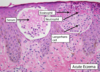

lichen planus

pruritic

purple

polygonal

papules

Wickam striae

symmetric distrubution

30-60 yo

hepatitis C, medication, contact allergen